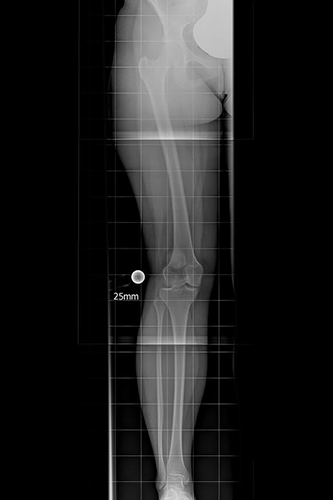

Für die Funktion des Kniegelenkes ist eine korrekte Beinachse unbedingt erforderlich. Durch die Verschiebung der Achse wird der innere Gelenkanteil überlastet und der Knorpelverschleiß nimmt stetig zu. Die Röntgenaufnahme im Stehen zeigt eine Verschmälerung des in- neren Gelenkspaltes. Wir sprechen von einer Varusgonarthrose. Die häufigsten Ursa- chen der einseitigen Abnutzung des Knorpelbelages finden wir nach Entfernung eines Meniskus. Ohne operative Korrektur der Beinachse nimmt die Fehlstellung und die Schmerzsymptomatik weiter zu.

Bei der operativen Geradstellung der Beinachse handelt es sich um einen gelenkerhaltenden Eingriff, der die Druckbelastung des geschädigten Gelenkbereichs reduziert und dadurch das Fortschreiten der Arthrose verhindert oder zumindest verlangsamt. Im Röntgenbild sieht der Operateur das Ausmaß der Fehlstellung des Kniegelenkes und berechnet den gewünschten Korrekturwinkel. Die Geradestellung kann die endoprothetische Versorgung hinauszögern, führt zu guten Ergebnissen und hat sich als Behandlungsverfahren der innenseitigen (medialen) Arthrose des Kniegelenkes etabliert.